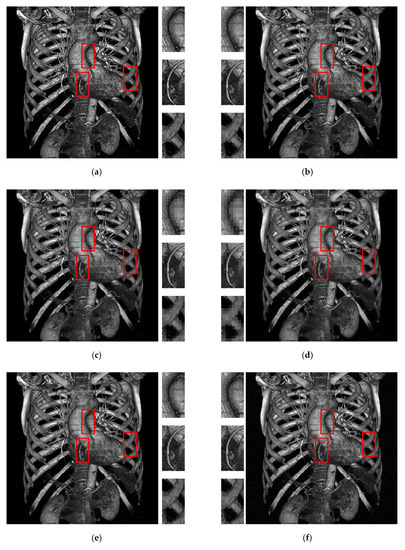

| Methods | Metrics | Test Images | |||||||

|---|---|---|---|---|---|---|---|---|---|

| Figure 6a | Figure 6b | Figure 6c | Figure 6d | Figure 6e | Figure 6f | Figure 6g | Figure 6h | ||

| AMBTC | HPSNR | 52.386 | 53.714 | 52.327 | 56.880 | 51.947 | 55.782 | 51.997 | 53.398 |

| MSSIM | 0.999989 | 0.999993 | 0.999991 | 0.999998 | 0.999988 | 0.999996 | 0.999989 | 0.999992 | |

| [17] | Payload | 55705 | 70735 | 65290 | 139045 | 94285 | 138550 | 93385 | 99745 |

| HPSNR | 45.611 | 47.074 | 46.000 | 50.547 | 45.043 | 48.918 | 45.278 | 46.718 | |

| MSSIM | 0.985154 | 0.987358 | 0.99123 | 0.991295 | 0.991393 | 0.997105 | 0.992532 | 0.991948 | |

| [20] | Payload | 85225 | 100375 | 94090 | 168190 | 124075 | 168355 | 104503 | 111643 |

| HPSNR | 43.593 | 44.052 | 43.417 | 43.274 | 41.751 | 41.757 | 45.095 | 46.517 | |

| MSSIM | 0.944949 | 0.93087 | 0.944172 | 0.831976 | 0.840213 | 0.748125 | 0.992271 | 0.991502 | |

| [22] | Payload | 61799 | 78833 | 72662 | 156251 | 105523 | 155690 | 90355 | 93070 |

| HPSNR | 45.451 | 46.861 | 45.758 | 49.688 | 44.980 | 48.722 | 45.223 | 46.670 | |

| MSSIM | 0.984876 | 0.986678 | 0.990819 | 0.988496 | 0.991152 | 0.996853 | 0.992462 | 0.992346 | |

| Ours | Payload | 104152 | 100490 | 108296 | 148264 | 125192 | 148664 | 124464 | 128712 |

| HPSNR | 52.402 | 53.653 | 52.489 | 56.008 | 52.777 | 56.152 | 52.644 | 53.989 | |

| MSSIM | 0.999990 | 0.999994 | 0.999992 | 0.999998 | 0.999989 | 0.999996 | 0.999990 | 0.999993 | |